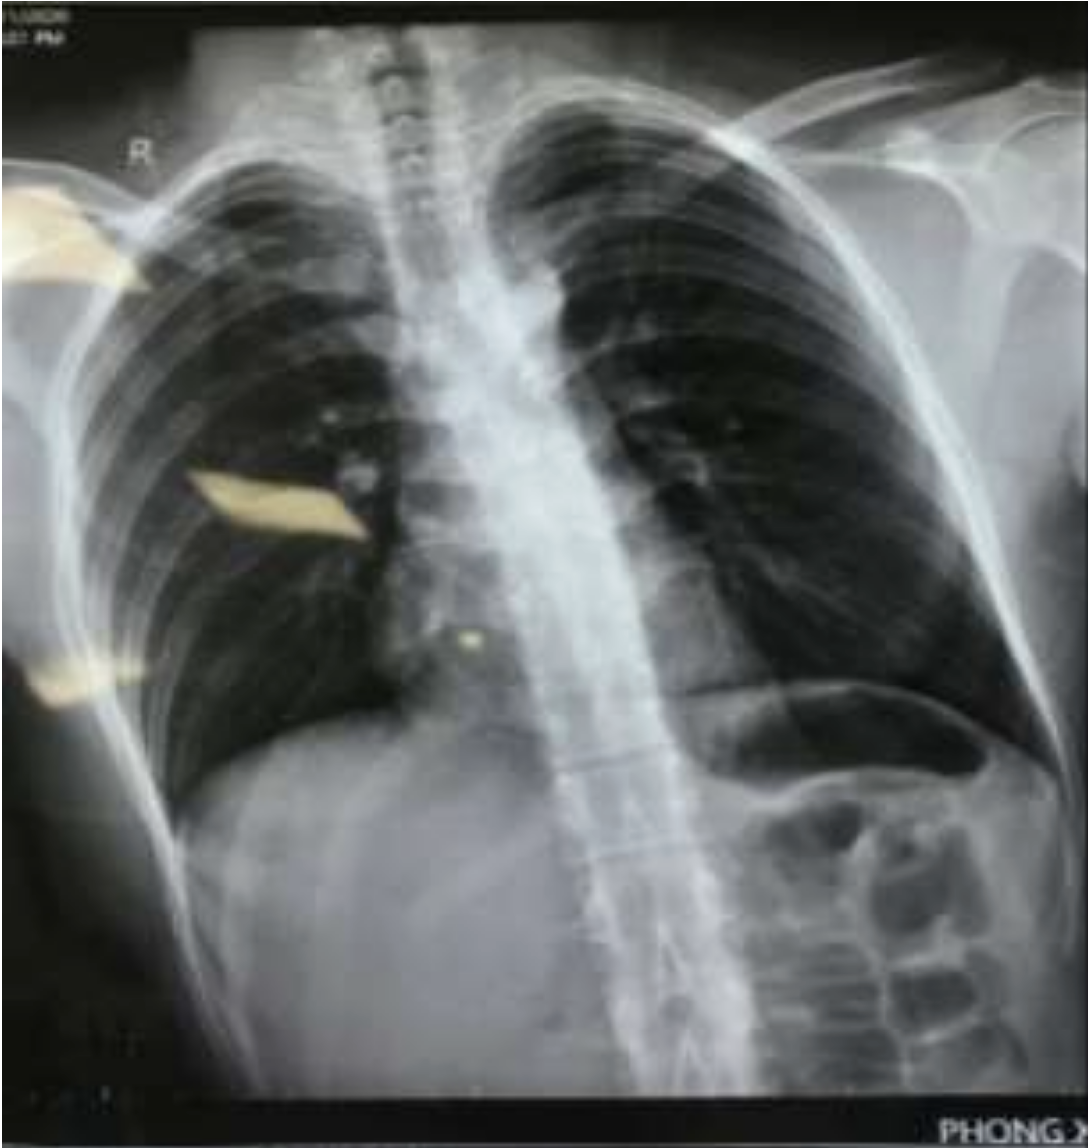

Báo cáo ca lâm sàng: Phẫu thuật bệnh nhân vết thương thấu phổi và thấu tim do tự đâm kết hợp bỏng thực quản do chất tẩy rửa

Phẫu thuật bệnh nhân vết thương thấu phổi và thấu tim do tự đâm kết hợp bỏng thực quản do chất tẩy rửa